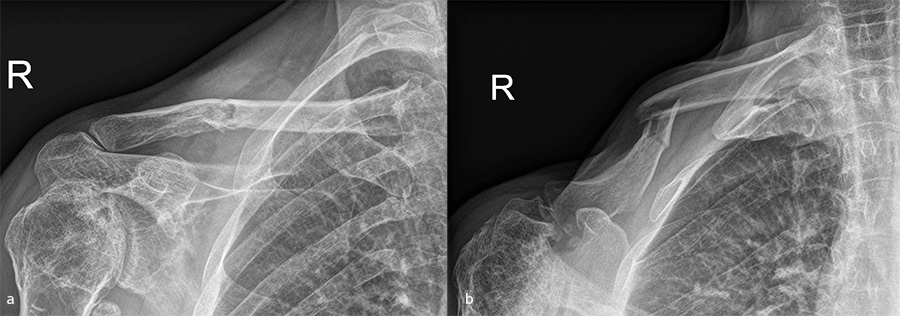

Case 2: shaft plate

A 54-year-old man sustained a mid-shaft fracture to his right clavicle following a 2 m fall from a ladder (Fig 13). Intraoperative images show plate placement and screw insertion (Fig 14). Postoperative image depicting minimal incision size for plate insertion before wound closure (Fig 15). Image shows the fracture healing at 6 weeks’ follow-up (Fig 16).